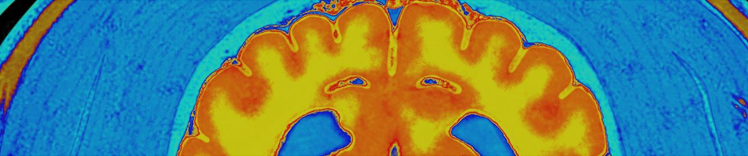

NEURONENMASSE UND HIRN-MRT

Veränderungen im alternden Gehirn

Zu den physischen Veränderungen des Gehirns, die mit dem Altern einhergehen, gehören:

- Atrophie (Schrumpfung) des Gewebes in einigen Regionen

- erhöhtes Ventrikelvolumen

- Verlust von Neuronen und Synapsen und verminderte Bildung neuer Neuronen

- Anhäufung von abnormen Proteinen

- Reduzierte Glukoseverwertung